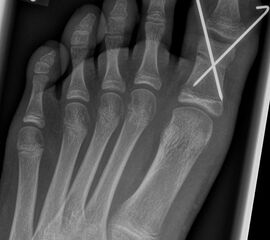

Abb. 2 a-c: offene Wachstumsfugen MT I Basis und Zehen (a), teilweise geöffnete Wachstumsfugen (b) und geschlossene Wachstumsfugen (c).

Zum Lesen der Bildbeschreibung und zur Vollansicht bitte die Bilder anklicken. Bilder: A. Helmers.